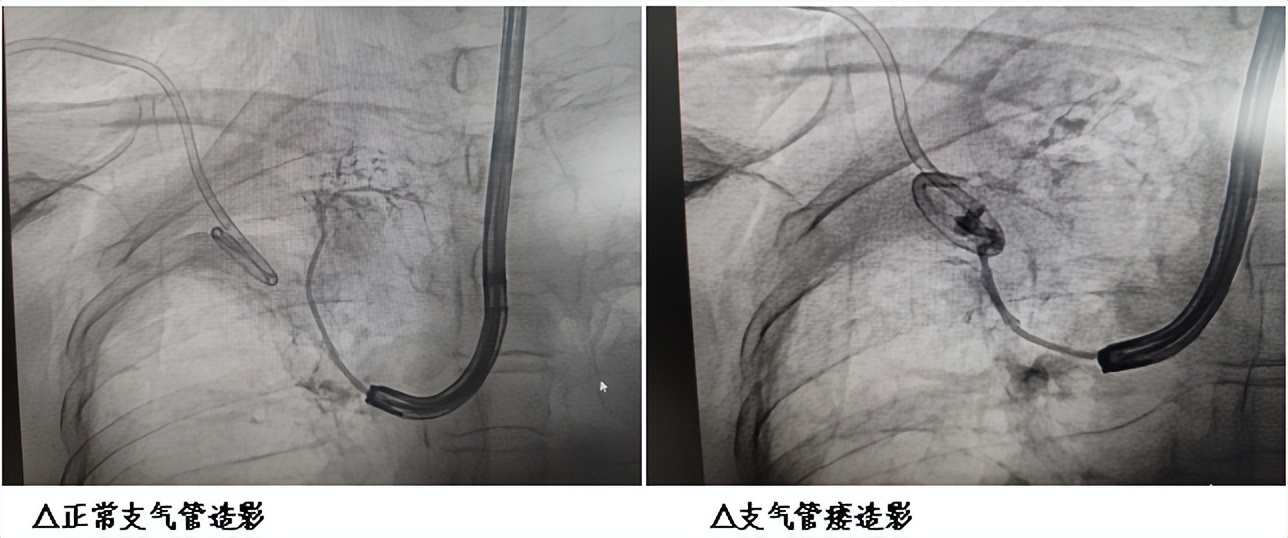

在与患者及家属充分沟通手术方案、风险,并签署知情同意后,手术正式启动。术中,医生先通过纤维支气管镜,精准找到张阿姨右肺下叶背段残端的瘘口;再借助DSA(数字减影血管造影)的精准引导,将微导管精准送入瘘口,通过造影确认瘘口形态和大小后,顺利完成封堵治疗。